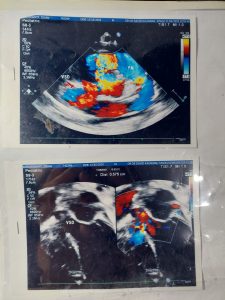

Penyakit : Bocor Jantung

Datang ke tempat praktek Dokter Royke pada tanggal 10 Agustus 2021, dengan keadan pada tubuh ada biru-biru dan mudah terkejut. Diagnosis oleh dokter anak adalah Bocor Jantung. Diberikan oleh dokter anak Captopril 3×0,3 mg/kg BB.

Diagnosa dokter anak Hasil USG 11-6-2021